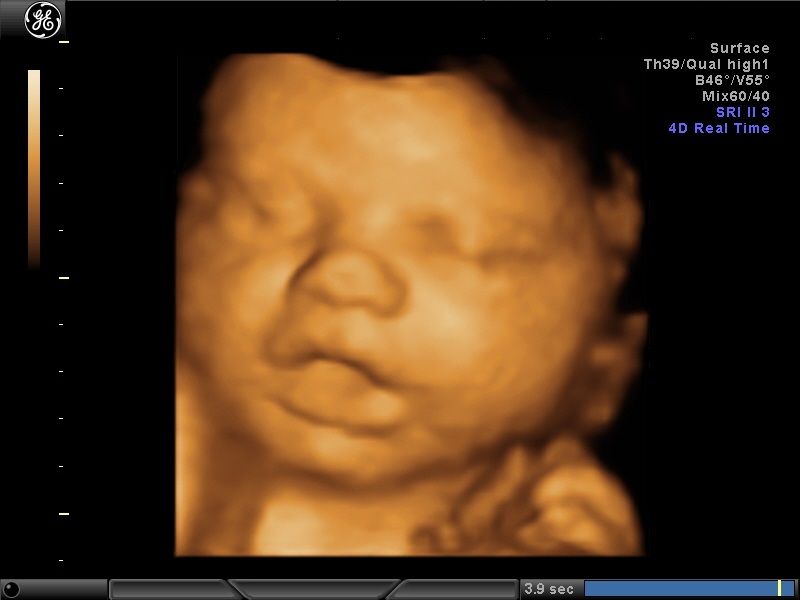

Wykonuję tam około 600 badań „I trymestru ciąży” rocznie, co daje łącznie około 1200 badań z „II trymestrem ciąży” włącznie. Od 15 lat w swoim gabinecie również wykonuję badania prenatalne I, II i III trymestru ciąży w znacznej ilości. To umożliwia mi osiągnięcie doskonałych wyników w diagnostyce tych badań, co stawia mnie w czołówce specjalistów diagnostyki prenatalnej.

Większość swojej kariery zawodowej spędziłem na sali porodowej oraz patologii ciąży. Aktualnie pracuję na sali porodowej. Mam 15-letnie doświadczenie w diagnostyce prenatalnej poparte dużą ilością przebadanych pacjentek i posiadam najszerszy wachlarz certyfikatów z zakresu ultrasonografii płodowej. Corocznie uczestniczę w szkoleniach i kursach ultrasonograficznych.

- diagnostyka prenatalna I,II i III trymestru ciąży z przepływami dopplerowskimi, testem podwójnym (PAPPA i B-HCG), oznaczanie DNA płodowego NIPTY, testy SANCO, NIFTY, VERACITY